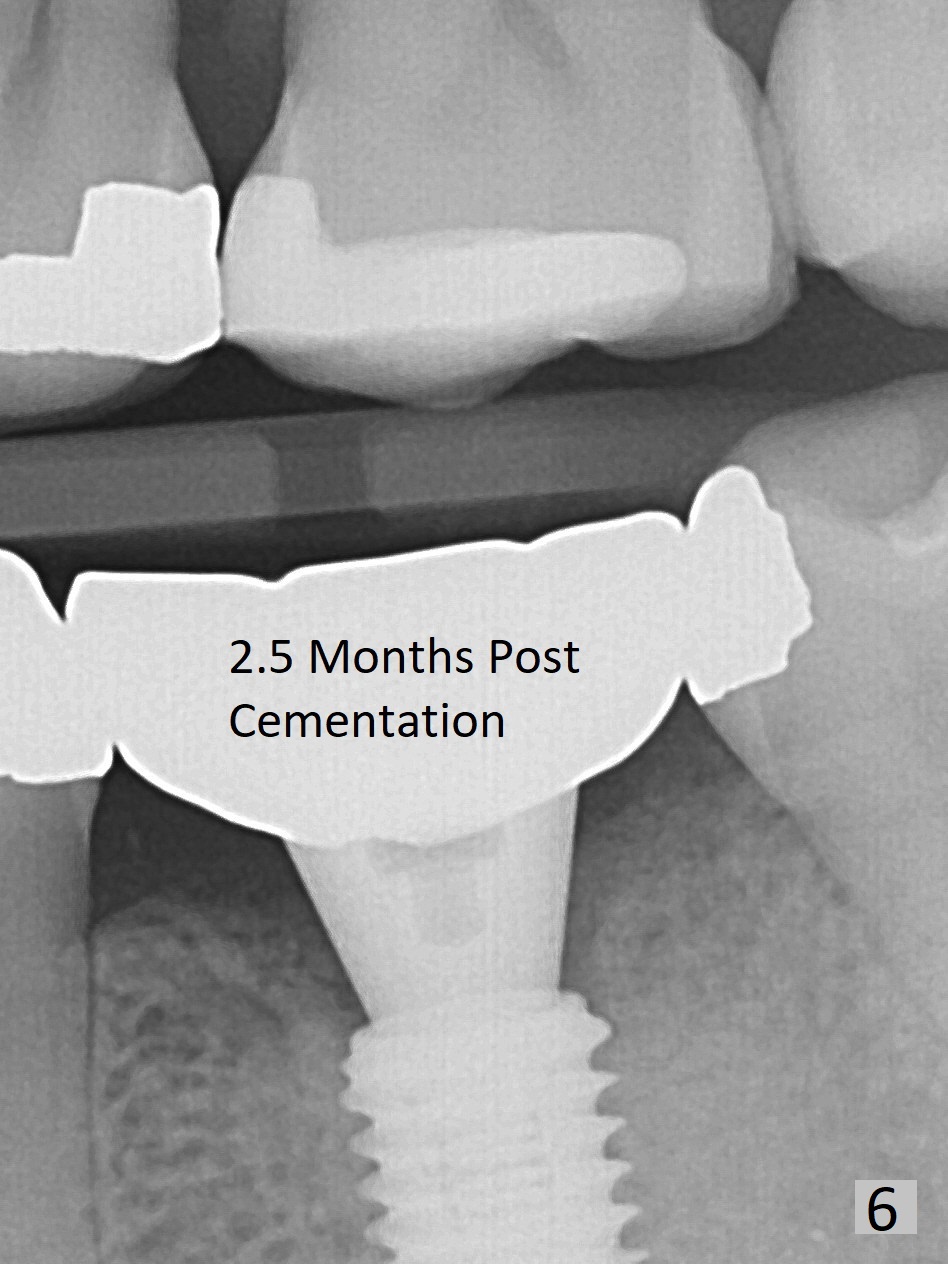

The ridge at #19 is slightly atrophic 5 months post socket preservation (Fig.1). The bone is long enough to hold a 11.5 mm long implant. There is no difficulty in inserting the corresponding drill (4.5x11.5 mm) into the metal sleeve, but the lower right posterior teeth prevent the implant handpiece from going downward completely when the handpiece accesses lingually. Because of the extra manipulation, a 5x10 mm implant achieves insertion torque of ~ 20 Ncm (Fig.2). The implant seems to be seated in the middle of the ridge (Fig.3). The bone density mesial to the implant increases 5 months postop (Fig.4), whereas that distal to the implant remains low 9 months postop (Fig.5). Bitewings taken 2.5 months post cementation (1 year postop, Fig.6,7) show subcrestal placement of the implant (advantage of guided surgery). The implant appears to be well protected; the crestal bone seems to cover the implant plateau. There will be little chance of thread exposure over years of use. The trabecular pattern around the implant is similar to that around the roots of the tooth #30 one year 7 months post cementation (2 years 4 months postop, Fig.8).